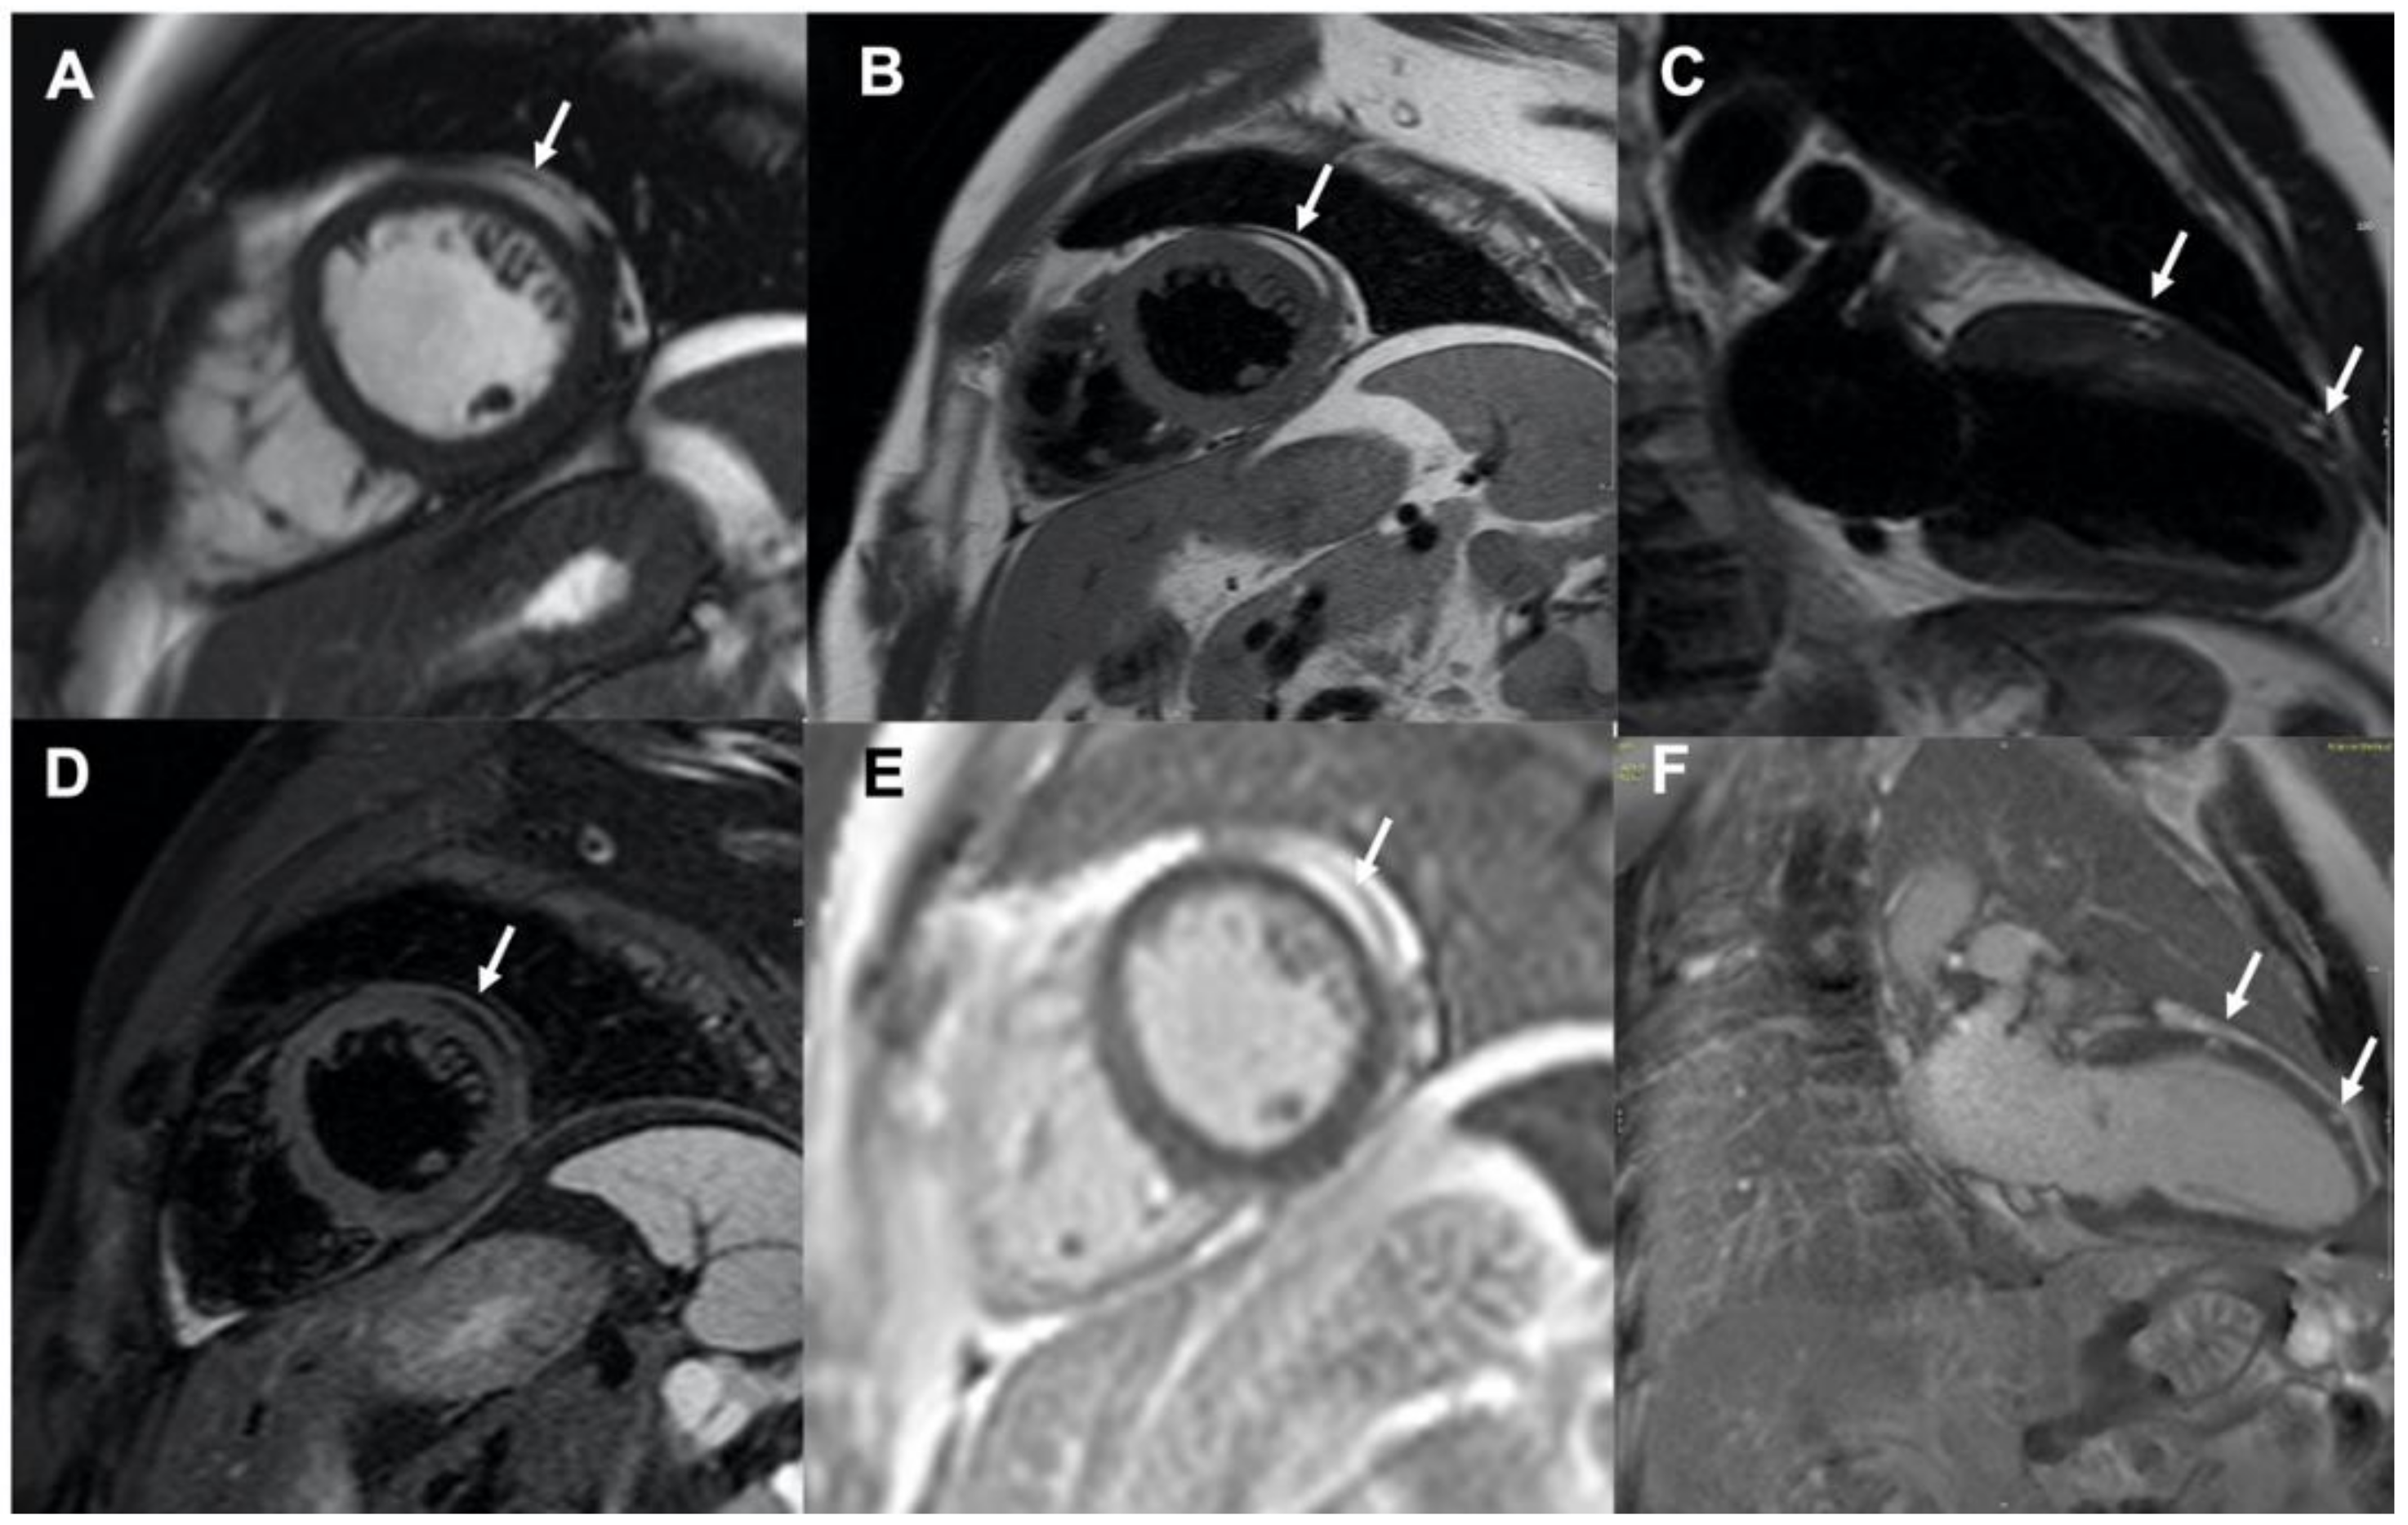

Magnetic Resonance Imaging of Intramyocardial Fat Deposition in Tuberous Sclerosis

Tsoumani, Z.; Greaves, M.; Schmitt, M.; Nucifora, G. Magnetic Resonance Imaging of Intramyocardial Fat Deposition in Tuberous Sclerosis. Diagnostics 2020, 10, 1031. https://doi.org/10.3390/diagnostics10121031